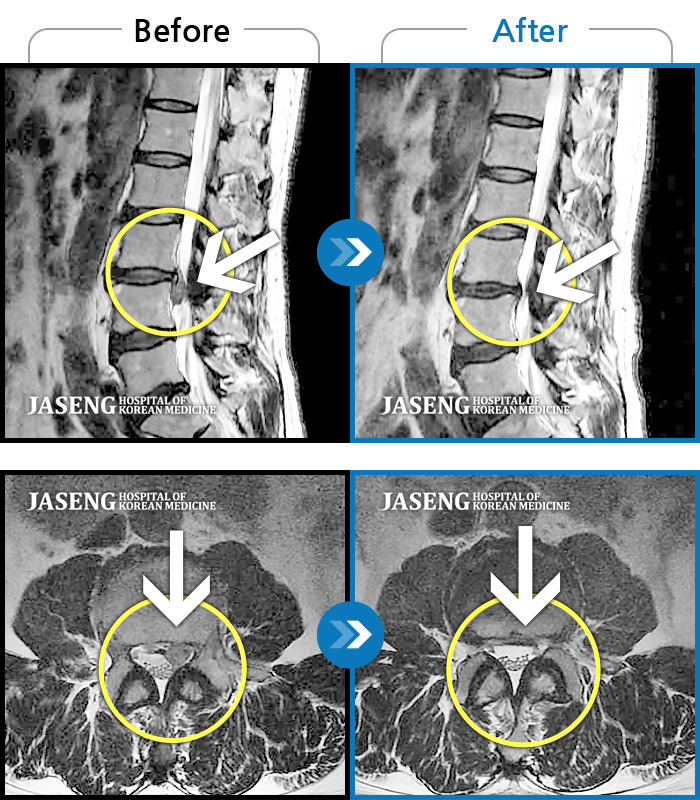

허리디스크

잠실 · 한상욱 원장

허리, 우측 엉치와 다리 후면 및 발끝까지 저림과 통증이 심하고 힘까지 빠진다.

촬영시기

2022.06.15 ~ 2022.11.11

2022.12.02

조회수 487